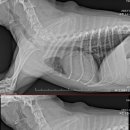

중랑구 상봉동 동물병원 루시드에서는 이런 증상으로 내원한 아이들을 매달 진료하고 있습니다. ​ ​ 해당 질환은 중성화를 하지 않은 암컷 반려묘에게서 자주 발생...및 응급 처치로 중증 환자에 대한 빠른 대응 가능 정형외과·신경외과 특화 의료 서비스 슬개골 탈구, 십자인대 단열, 디스크 수술 등 고난도 외과 수술...